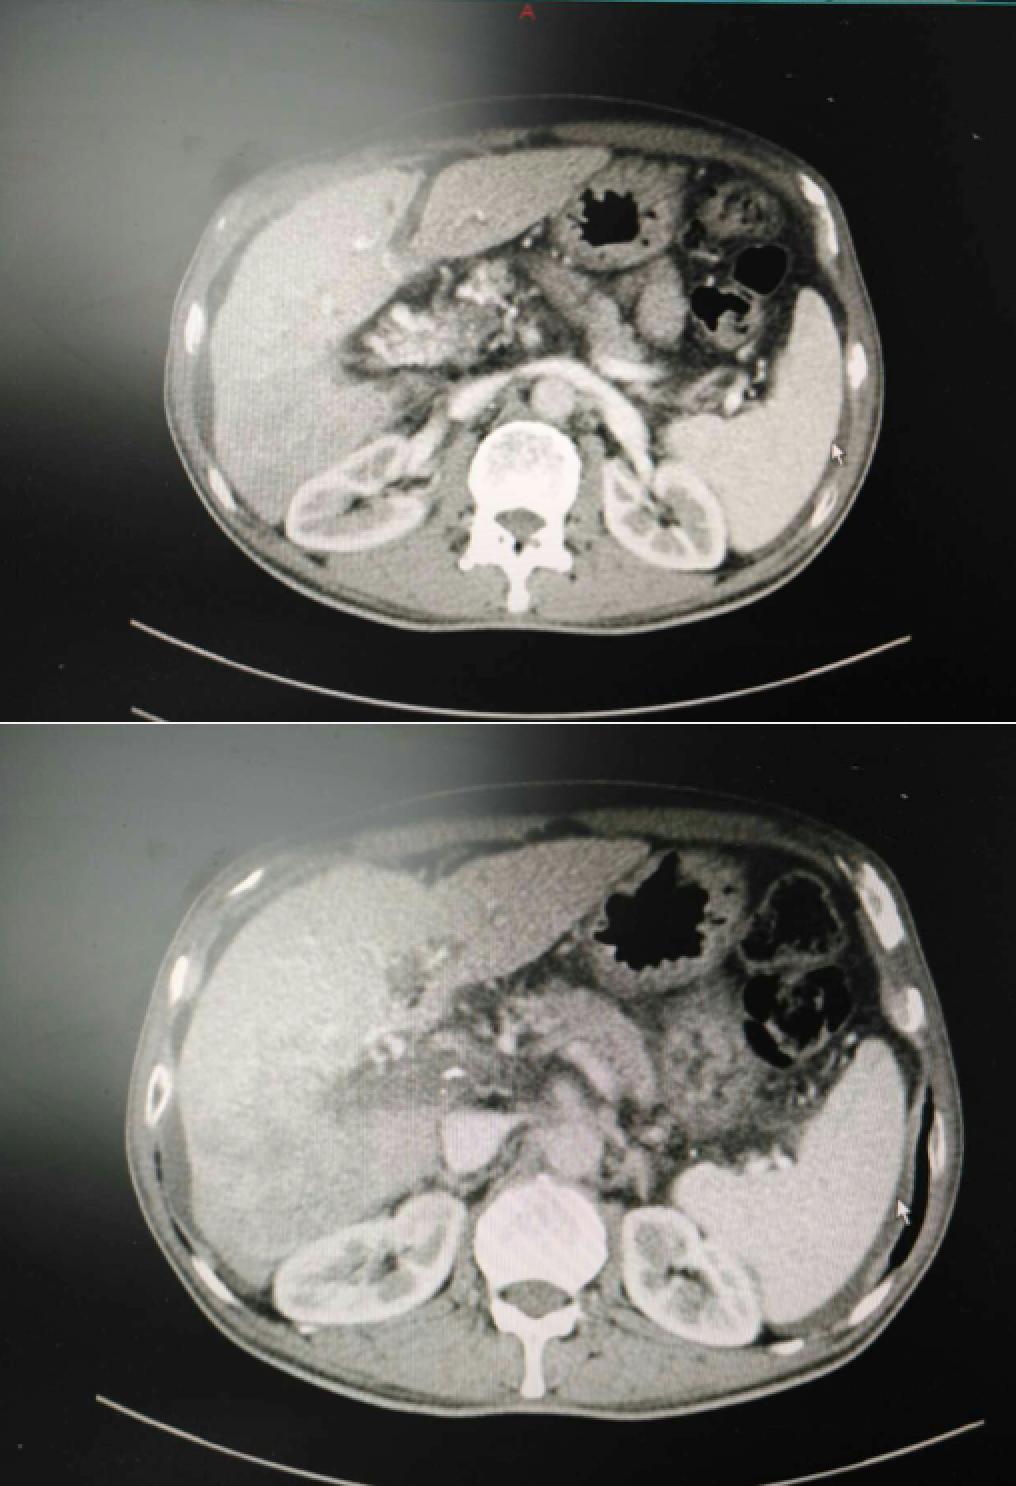

患者相关影像资料